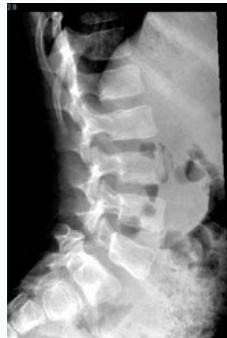

Spondylolisthesis

Definition: One vertebra moves over another (انترلاق فقرى)

- Lateral view: Shows vertebral slip